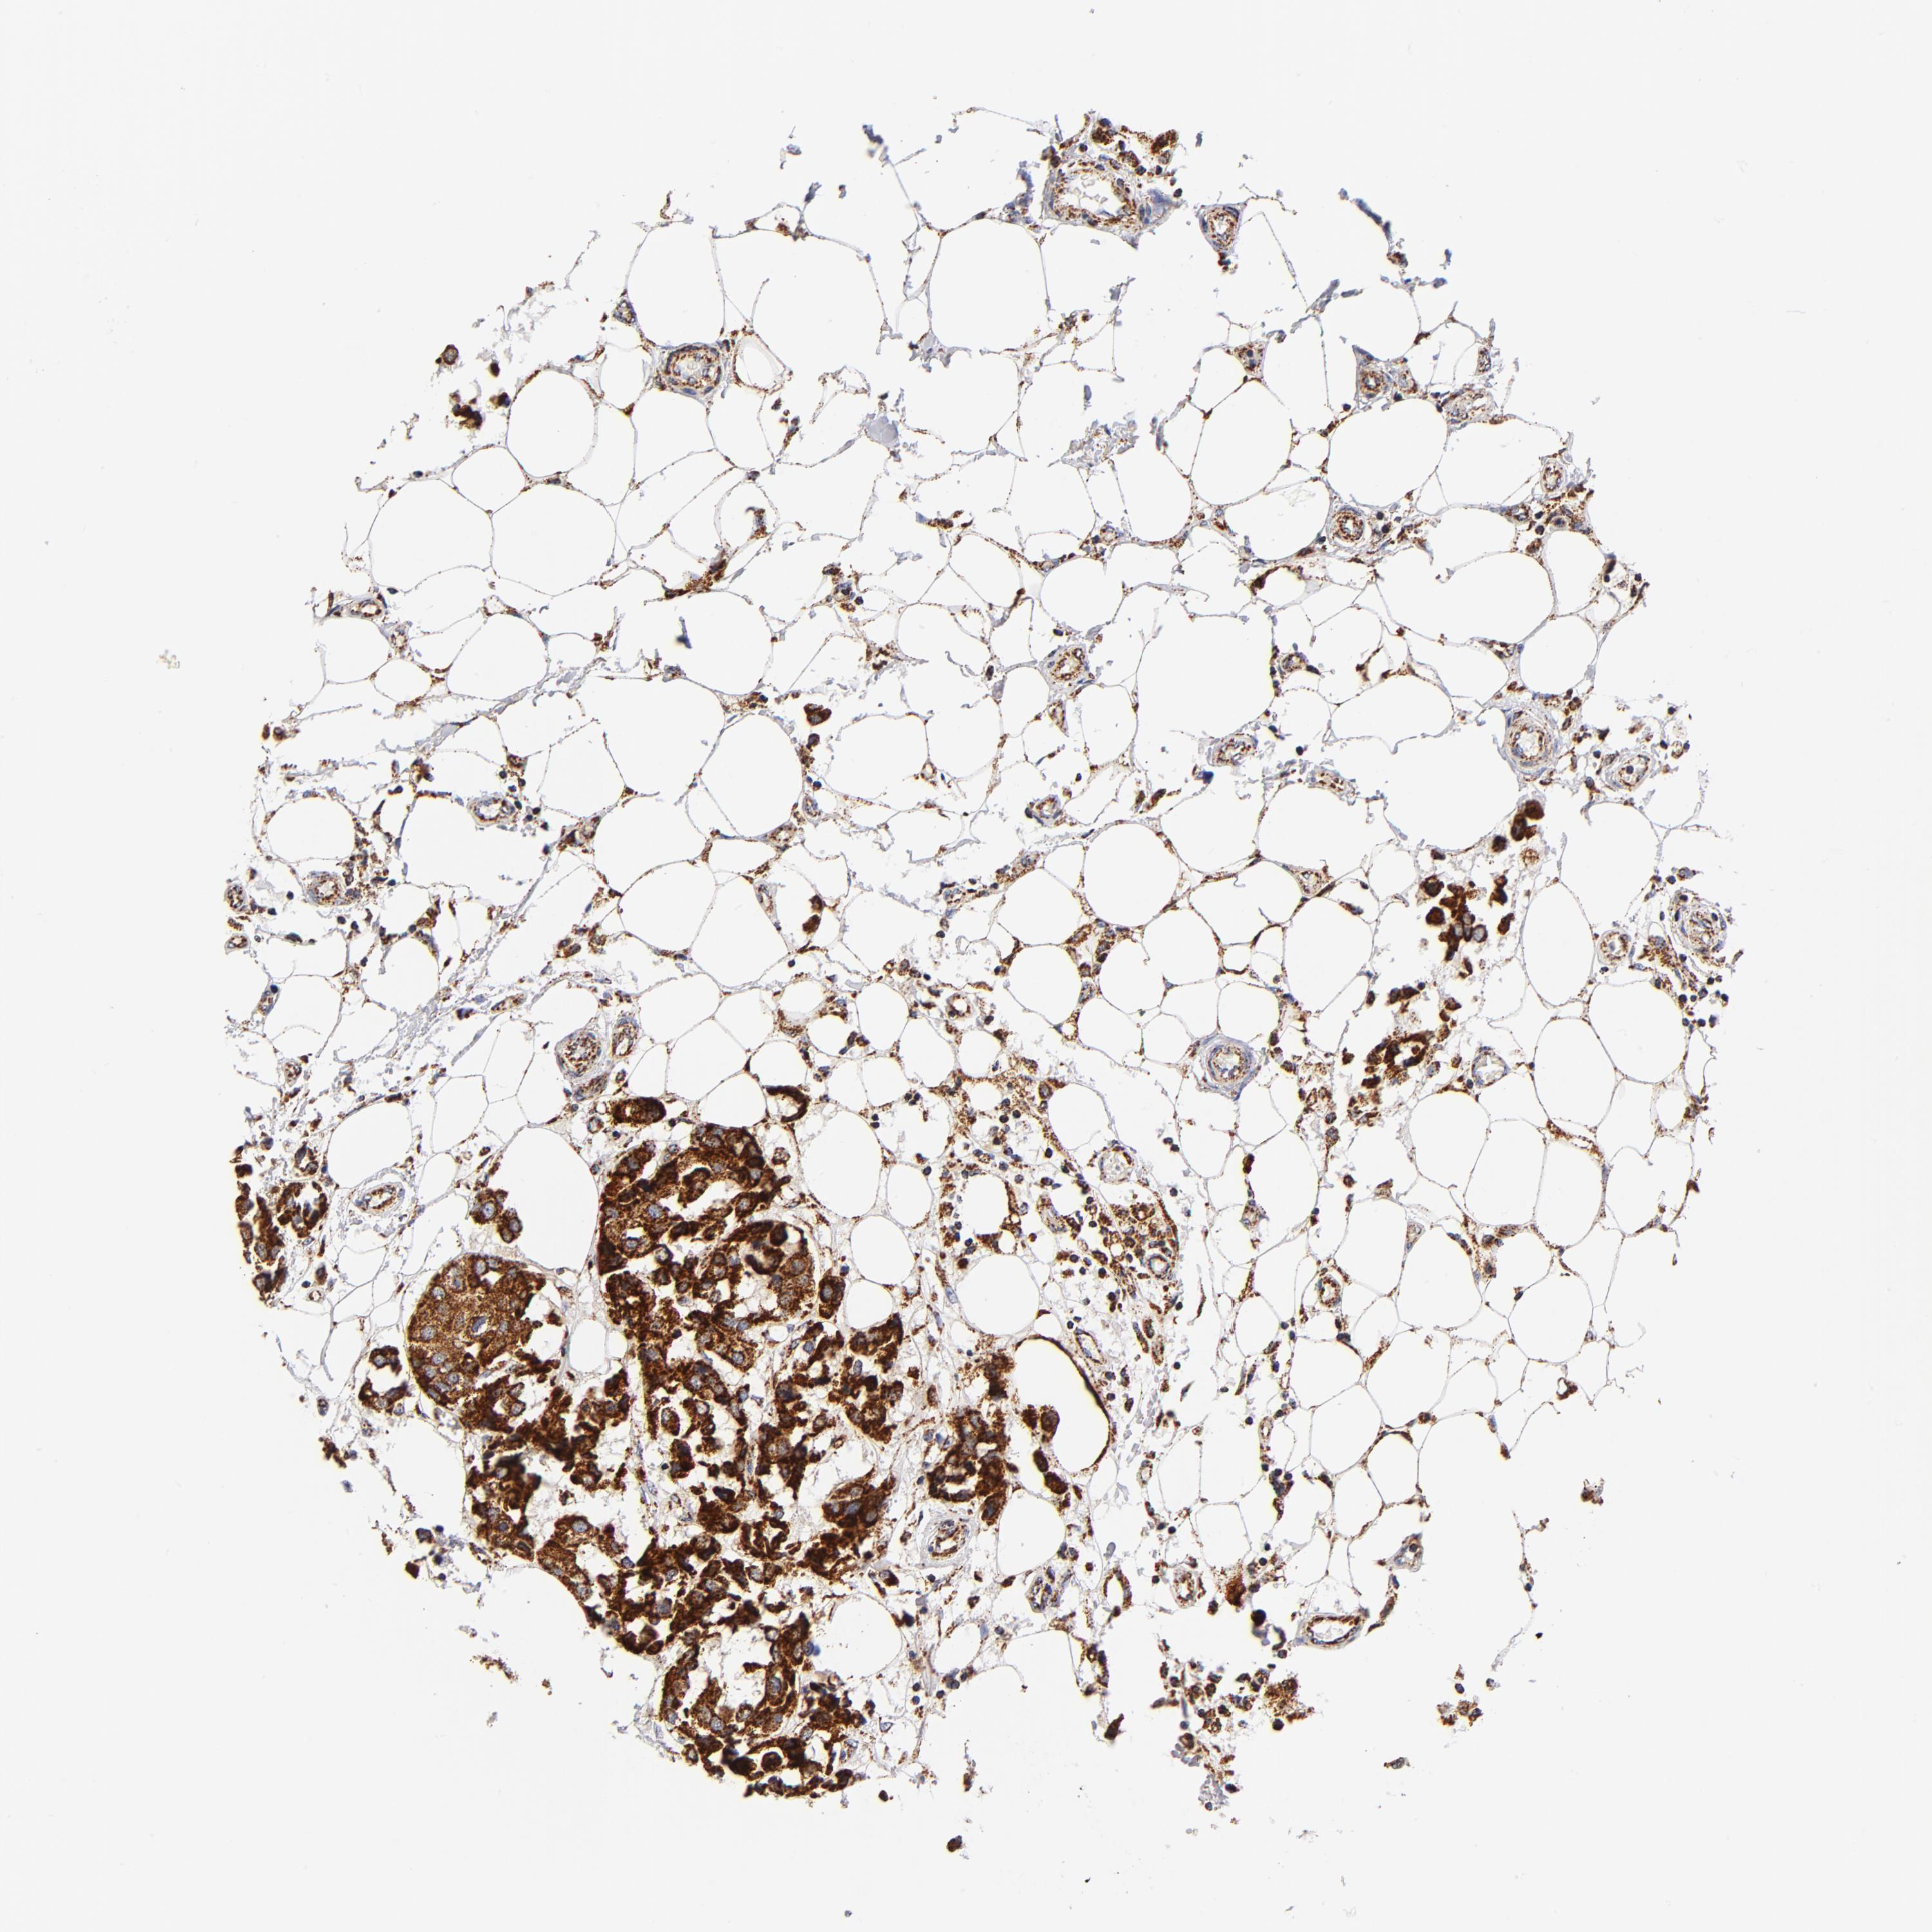

CANCER BREAST CANCER Show tissue menu

BRCA TCGA BRCA VALIDATION PROTEIN EXPRESSION

ANTIBODIES

AND

VALIDATION